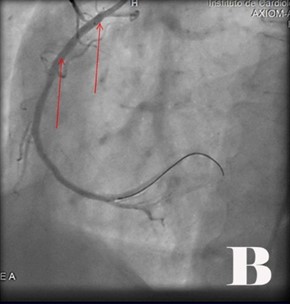

Fig. Abordaje invasivo emergente en paciente con Angina inestable de Alto riesgo y cambios electrocardiográficos atípicos con FEVI muy baja.

Fig. Se visualizó obstrucciones largas proximal y distal de 90 % de coronaria derecha (CD) (2A). Se realizó ACTPs y coloco 2 Stens convencionales (2B). Obstrucción de tercio proximal de 90 % de arteria coronaria de descendente anterior (DA) y del 95 % de la circunfleja izquierda (CX) (2C), se le realizó ACTP y colocó Stens a la DA fármacoactivo pero por el riego-beneficio se decidió no hacer nada en CX (2D).